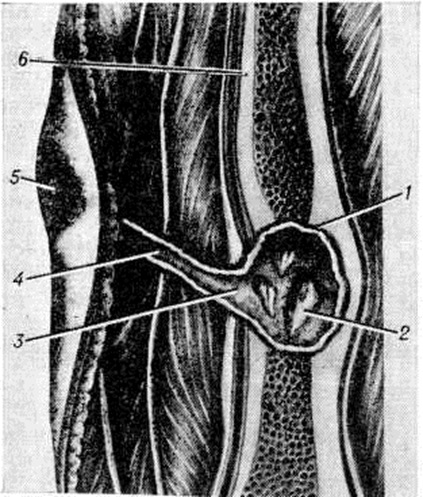

Воспаление начинается в мягких тканях краёв раны в виде диффузной воспалительной инфильтрации, вслед за которой на границе с зоной омертвения формируется демаркационная линия. Одновременно образуется экссудат, поступающий в полость раны и пропитывающий некротизированные ткани, подвергающиеся при этом расплавлению, а часто и гнилостному распаду. К 4— 5-му дню в зоне демаркационной линии образуются грануляции, обильно продуцирующие гной. К этому сроку проявляется и гнойное воспаление в отломках кости, которое протекает на границе с некротизированными тканями, сохраняя характер демаркационного. С началом нагноения омертвению могут подвергнуться связанные с периостом костные осколки и мягкие ткани, испытавшие коммоцию — зона резерва некроза по И. В. Давыдовскому. Очаг нагноения постепенно изолируется валом из грануляций, а в последующем и соединительнотканной капсулой. В нем располагаются свободные костные осколки, не удалённые при хирургической обработке раны, осколки, сохранившие связь с периостом, концы отломков, лишённые периоста, инородные тела, обрывки мягких тканей, распадающиеся кровяные свёртки (рисунок 3). Нагноение нередко распространяется в глубь мягких тканей и в толщу кости вдоль трещин и каналов, проделанных сместившимися в момент ранения костными осколками, что придаёт очагу сложные очертания (цветной рисунок 1).

В ходе нагноения в окружающих очаг тканях развёртываются пролиферативные и дистрофические процессы. В результате пролиферации тканей возникает гноеродная оболочка, а затем формируется костная мозоль (смотри полный свод знаний) с последующей консолидацией перелома или образуются лишь костные разрастания по краям отломков (рисунок 4). Возникшая костная мозоль включает в себя гнойники с секвестрами (цветной рисунок 2) и играет т. о. роль секвестральной капсулы, из которой свищевые ходы ведут на поверхность кожи (рисунок 5). Дистрофические изменения выражаются в диффузной рарефикации, а позже в очаговой эбурнеации кости (смотри полный свод знаний) в зоне образования мозоли. В окружающих мягких тканях и в соседних суставах развиваются явления атрофии.

Различают ранние и поздние гнойно-воспалительные осложнения огнестрельных переломов костей. Ранние осложнения, возникающие непосредственно после ранения, в большинстве случаев связаны с гнилостным распадом костного мозга или гнойным воспалением его внутри костномозгового канала и характеризуются бурным клинические, течением с выраженными общими реакциями, как и при гематогенном Остеомиелит Поздние осложнения (спустя 1—2 месяцев после ранения) развиваются обычно вне костномозгового канала, главным образом в элементах опорной костной ткани; при этом наблюдается выраженное отграничение процесса и образование гнойной полости вокруг мёртвых костных осколков и инородных тел (рисунок 8). Репаративно-ре генеративные процессы, приводящие к патологический изменениям в виде гиперостоза (смотри полный свод знаний) и склероза плотной костной ткани (смотри полный свод знаний Остеосклероз), составляют сущность этого вида осложнений и обусловливают переход ранних его форм в хронические.